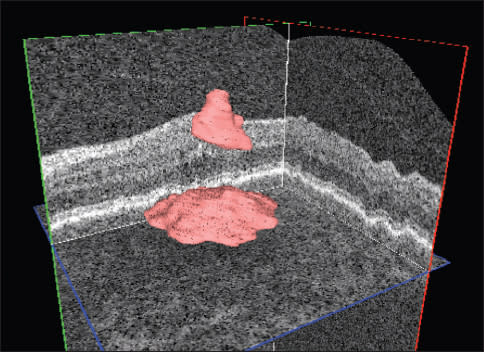

Figure 2. Automated quantification (above) and localization intraretinal and subretinal (below) fluid in a patient with AMD and choroidal neovascularization.

Disease management. With the advent of the anti-VEGF agents ranibizumab and bevacizumab, it has become clear that outer retinal and subretinal fluid is the main indicator of a need for anti-VEGF retreatment and that OCT can be used to predict disease activity and guide disease management.26-30

Disease management. OCT is particularly useful in the management of DME, allowing detailed assessment of retinal thickness and morphologic evaluation of the neurosensory retinal layers.51 Currently, OCT imaging is widely used to determine the extent and volume of retinal thickening. We expect that detailed analyses of retinal layer morphology and texture from OCT will allow direct, image-based treatment to be guided by computer-supported or automated quantitative analysis of OCT.